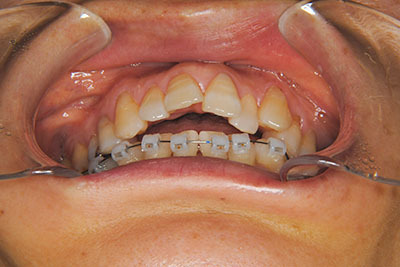

おとなの方でも矯正治療をあきらめないでください!

矯正歯科治療は子供の頃だけしかできない……

子供の頃に比べ大人になったら治療期間がすごく長い……

というようなイメージをお持ちではありませんか?

子供の頃に矯正治療を行う方が治療期間が短く済むというのは、確かですが、矯正治療は患者様の意識も重要です。

いくら歯が動き易くとも、本人がやる気でなければ効果は出ませんし、むし歯発生のリスクも高まります。おとなの方は顎の成長が終わっているため、治療の計画が立てやすいとも言えます。「もう大人だから…」とあきらめず、一度ご相談ください。

本格矯正治療の詳しい説明は小児矯正治療/本格矯正治療ページを御覧ください。